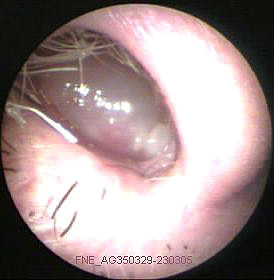

JFC Otitis media serosa de origen disbárico.

JFC Otitis media serosa izquierda.